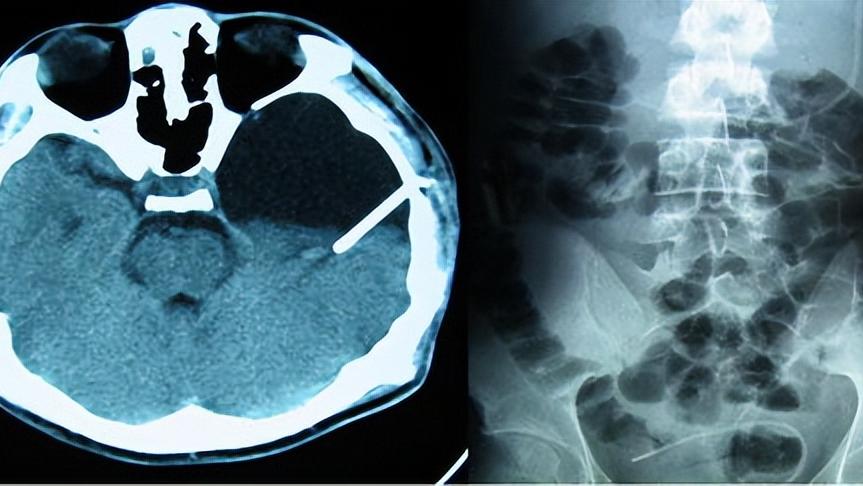

三、准确快捷?不出现不舒服症状尽量不要做脑CT

CT目前大概分为两种工作方式,其一就是普通平扫,患者只用直接躺在CT机器上面,大概几分钟就会完成扫描。而另外一种则是增强扫描,即在平扫的基础上,静脉注射碘对比剂。后者会随着血液循环,流经身体各个组织。此时我们能够更清楚观察病变组织的情况,和周围的正常组织作对比,看具体的病变情况。

通过检查具体方式,我们不难看出来CT检查方便,定位准确,并且无创伤,患者也受不到什么痛苦,而且价格便宜。因此对于脑部疾病,CT通常是第一选择。

因为这一种通过X光线断层扫描获得图像的检查方式,本身就会释放定量的辐射。这些电离辐射能够破坏人体内某些大分子结构,从而损伤细胞,最后可能累及到机体各组织。而脑细胞受损或者死亡后,本身就很难修复,因此脑部CT相对来说伤害会更显著一点。

目前做一个头颅CT的平均辐射剂量会达到2mSv左右,我们连续坐20小时飞机也才0.1mSv而已,每天抽20支烟平均也才被辐射到1mSv。我国放射标准中规定,对于放射工作人员来说,每年剂量限制是50mSv。

所以其实单独做一次CT对人体的影响是微乎其微,但是考虑到它毕竟存在伤害性。因此对于我们来说,平时非必要情况下,还是建议能不做就不要做。